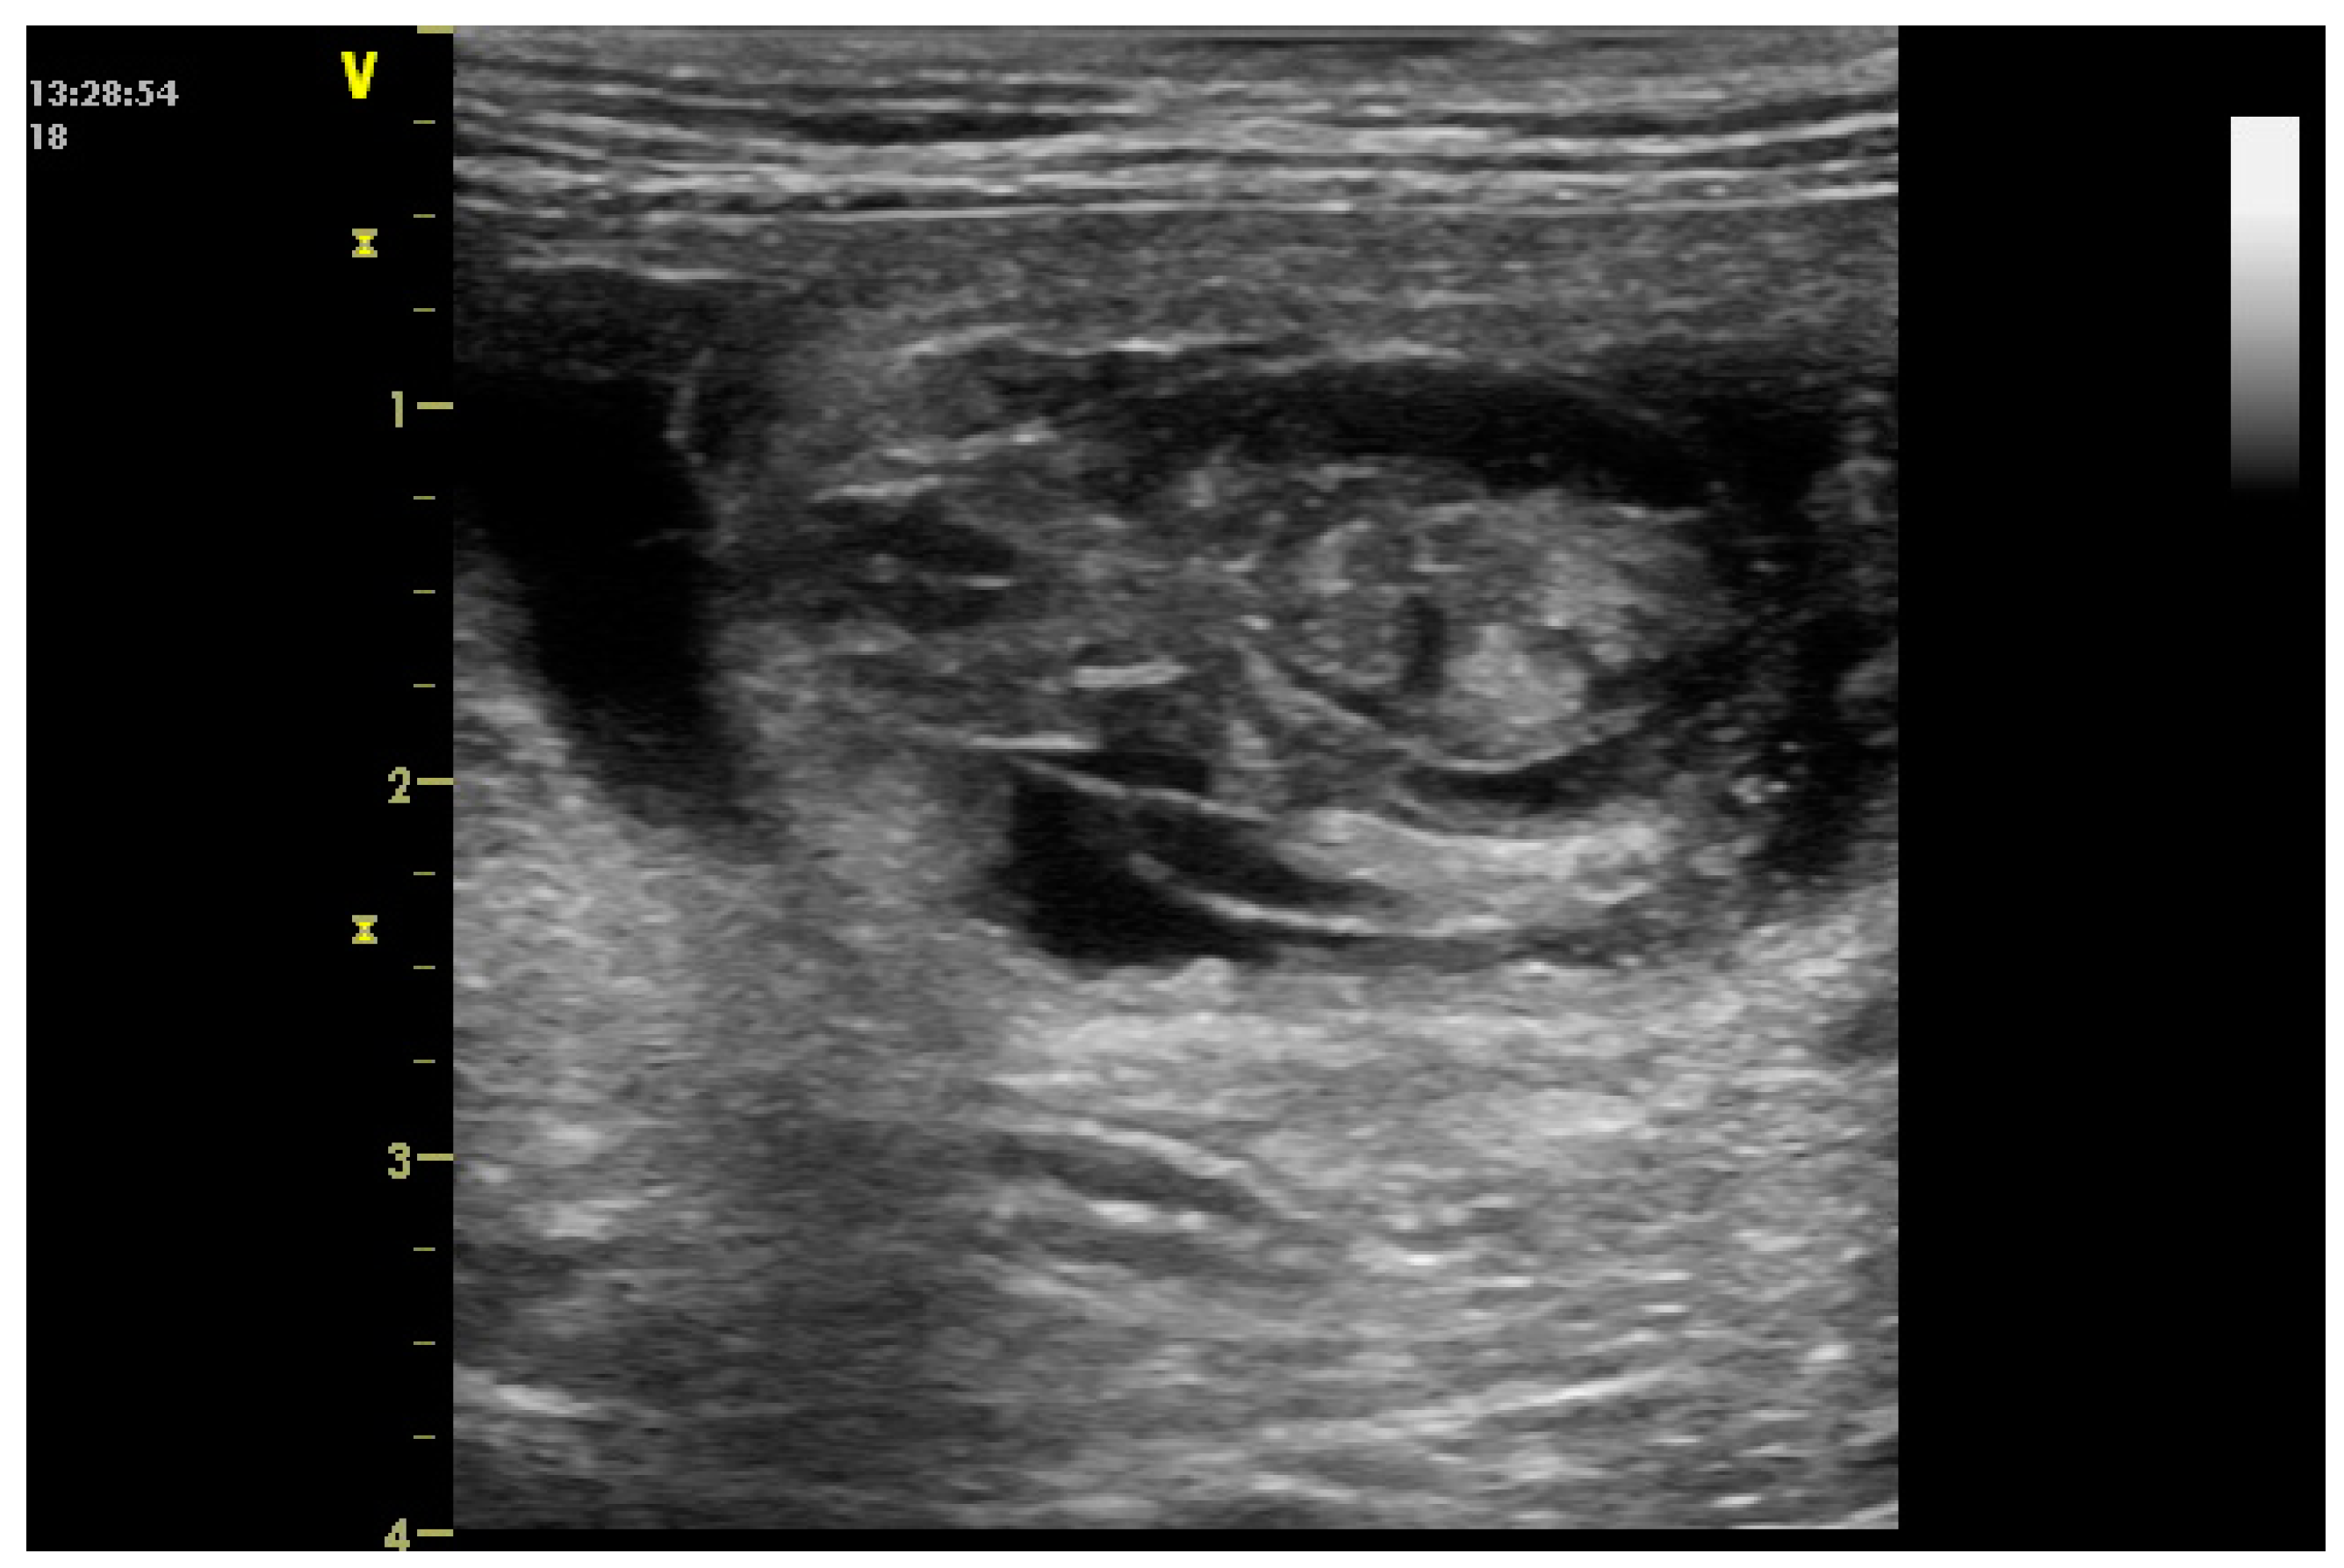

2.3. Uterine Pathology